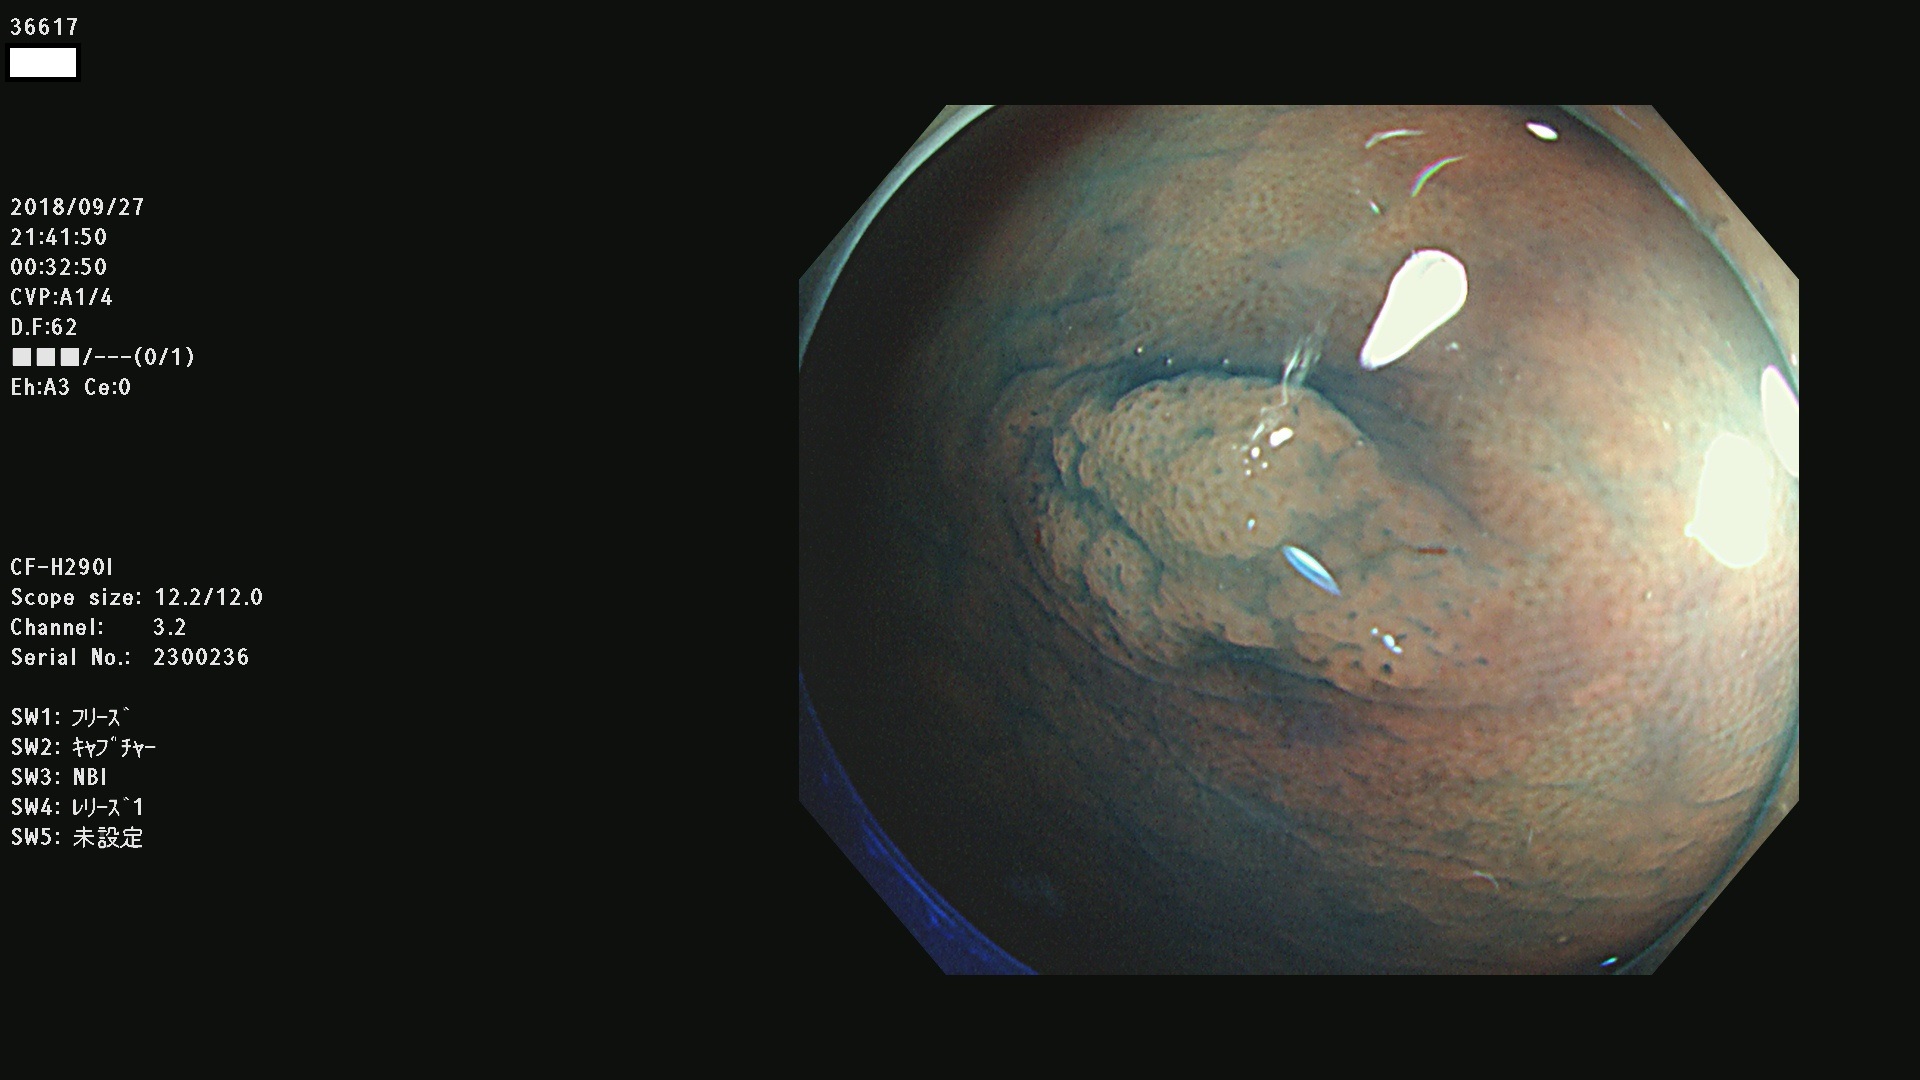

36600 36601 36603 36605 36606 36608 36609 36610 36611 36612 36613 36615 36617 36620 36621 36624 36625 36626 36627 36628 36629 36631(SSAPのみ) 36632 36633 36634 36636(SSAPのみ) 36637(SSAPのみ) 36639 36640 36642 36643 36644 36646 36647 36648 36649(SSAPのみ) 36650(SSAPのみ) 36652 36653 36654 36655(SSAPのみ) 36656 36657 36658 36659 36660 36661(SSAPのみ) 36665 36668 36669 36672 36673 36676 36677 36678 36679 36681 36682 36683 36684 36685 36687(SSAPのみ) 36691 36692 36693 36694 36695 36696 36697 36699(SSAPのみ)

発見困難で危険性の高い平坦型病変(上記100名より抽出)

カルチノイド